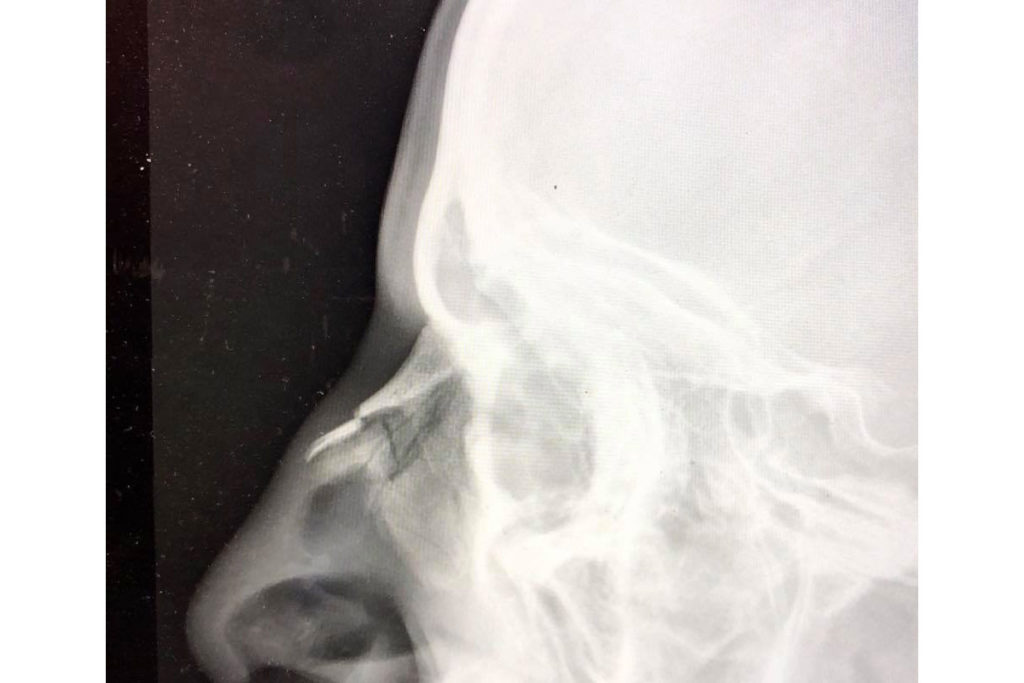

Der Olympia Test in Tokio wird Lukas Hollaus nicht nur wegen des starken 24. Platzes wohl noch länger in Erinnerung bleiben. Denn seit kurzem steht fest: der Schlag den der 32-jährige auf der Schwimmstrecke auf die Nase bekommen hatte, war so hart, dass sie gebrochen ist.

„Das haben sowohl die Untersuchungen im LKH als auch bei einem Spezialisten ergeben“ sagt der Niedernsiller. Unter diesen Umständen ist die Leistung des Pinzgauers in Japan noch höher einzuschätzen.